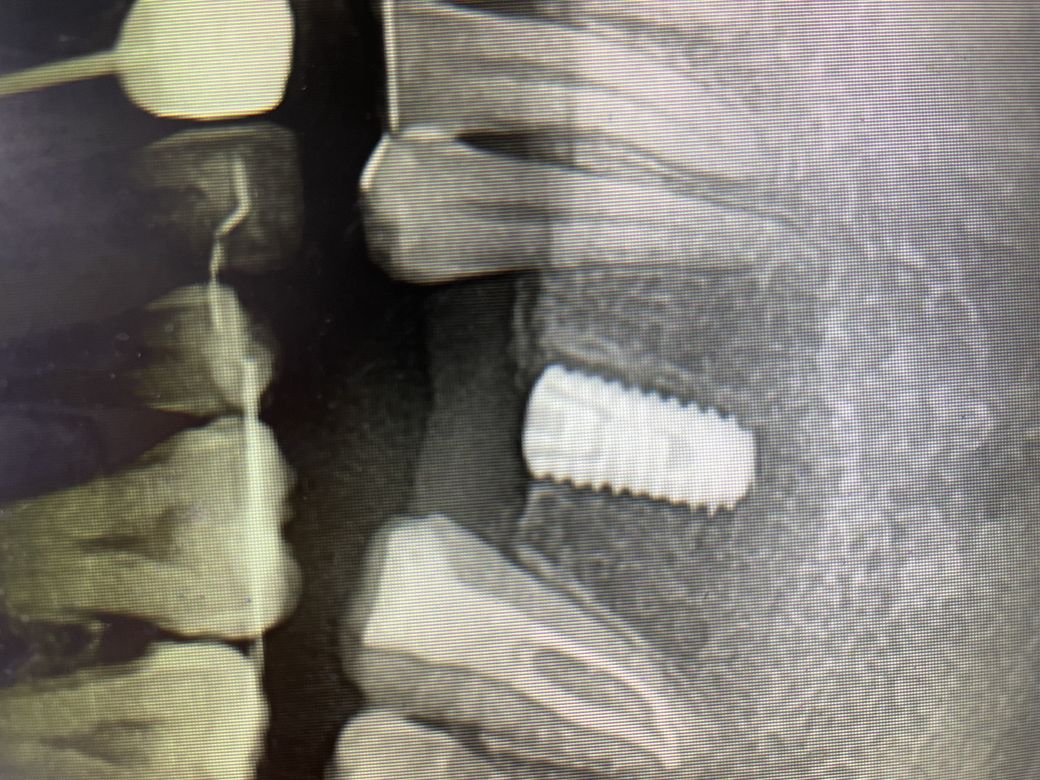

엑스레이 상으로는 식립이 잘 된간가요?ㅠㅠ

임플란트는 엑스레이상 문제없어보입니다.

확답을 드리긴 힘들지만 임플란트에는 큰 이상이 없어 보이긴 합니다.

해당 사진으로는 실밥이 보이지 않습니다. 실밥이 잔류되어 있는 것은 회복에 좋지 않습니다. 따라서 실밥이 맞다면 다시 치과를 내원하여 실밥을 제거하는 것이 필요합니다. 엑스레이 상에서 임플란트 픽스쳐 식립은 잘되어 있습니다. 따라서 실밥 잔류되어 있는 것만 제거하시면 될 것 같습니다.

엑스레이상으로 식립이 잘 되어있습니다.

방사선사진에서 임플란트 식립은 잘된것 같습니다.